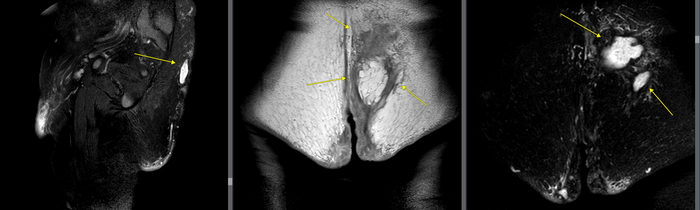

Вид сбоку справа, вид сверху на уровне ягодиц

Потом от главного свищевого входа отходит дополнительная ветка, идет через правую ягодицу и открывается в мошонку, формируя там флегмону.

Вид сбоку парацентрально слева, вид спереди кзади от крестца, вид сверху чуть ниже крестца

Также от главного свищевого хода отделяются еще две ветки и идут кверху через подкожную жировую клетчатку спины.

Вид сбоку слева, вид спереди кзади от крестца, вид спереди кзади от крестца

Медиальный свищ заканчивается на уровне крестца в подкожной жировой клетчатке, не открывается на кожу, образует полость с гноем; латеральный свищ тянется вверх, уходит за пределы исследования, открывается на кожу спины где-то на уровне грудного отдела позвоночника.